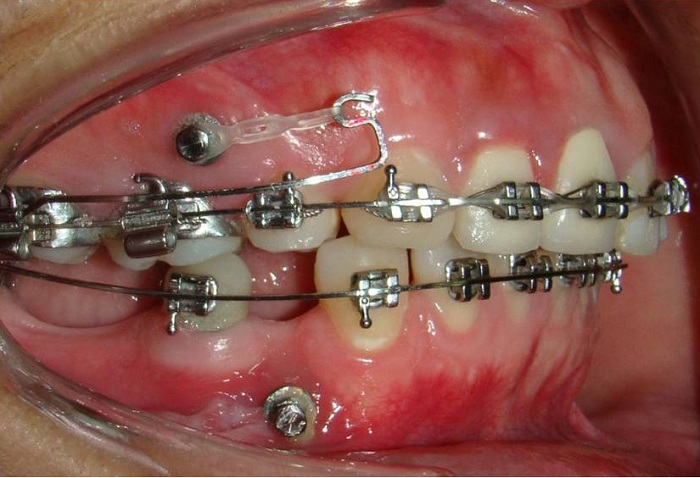

Sử dụng minivis

Minivis là những chiếc ốc vít nhỏ, được cắm sâu vào trong xương hàm tạo điểm neo giữ các khí cụ khác như lò xo, thun chuỗi,… để kéo khít khoảng trống khi nhổ răng.

Minivis là lựa chọn tối ưu trong các trường hợp điều trị hô, móm, khớp cắn sâu cần đưa nhóm răng cửa ra trước hoặc lùi về sau. Kỹ thuật nắn chỉnh răng của bác sĩ kết hợp với minivis sẽ giúp việc kiểm soát lực kéo cân bằng và chính xác hơn rất nhiều. Việc sử dụng minivis giúp đơn giản hóa quá trình chỉnh nha, không cần phải thiết kế hệ thống đặt lực phức tạp như trước kia. Vị trí đặt minivis có thể ở giữa các răng, hàm trên hay hàm dưới phụ thuộc vào từng trường hợp.

Quá trình cắm vis sẽ không có cảm giác đau nhức do bạn đã được gây tê trước khi tiến hành cắm. Sau khi thuốc tê tan hết bạn sẽ hơi ê nhức trong 1 – 2 ngày đầu chứ không quá đau như nhiều người vẫn nghĩ. Ngoài ra bạn cũng sẽ được bác sĩ kê thuốc giảm đau, viêm giúp giảm đau hiệu quả nhất.